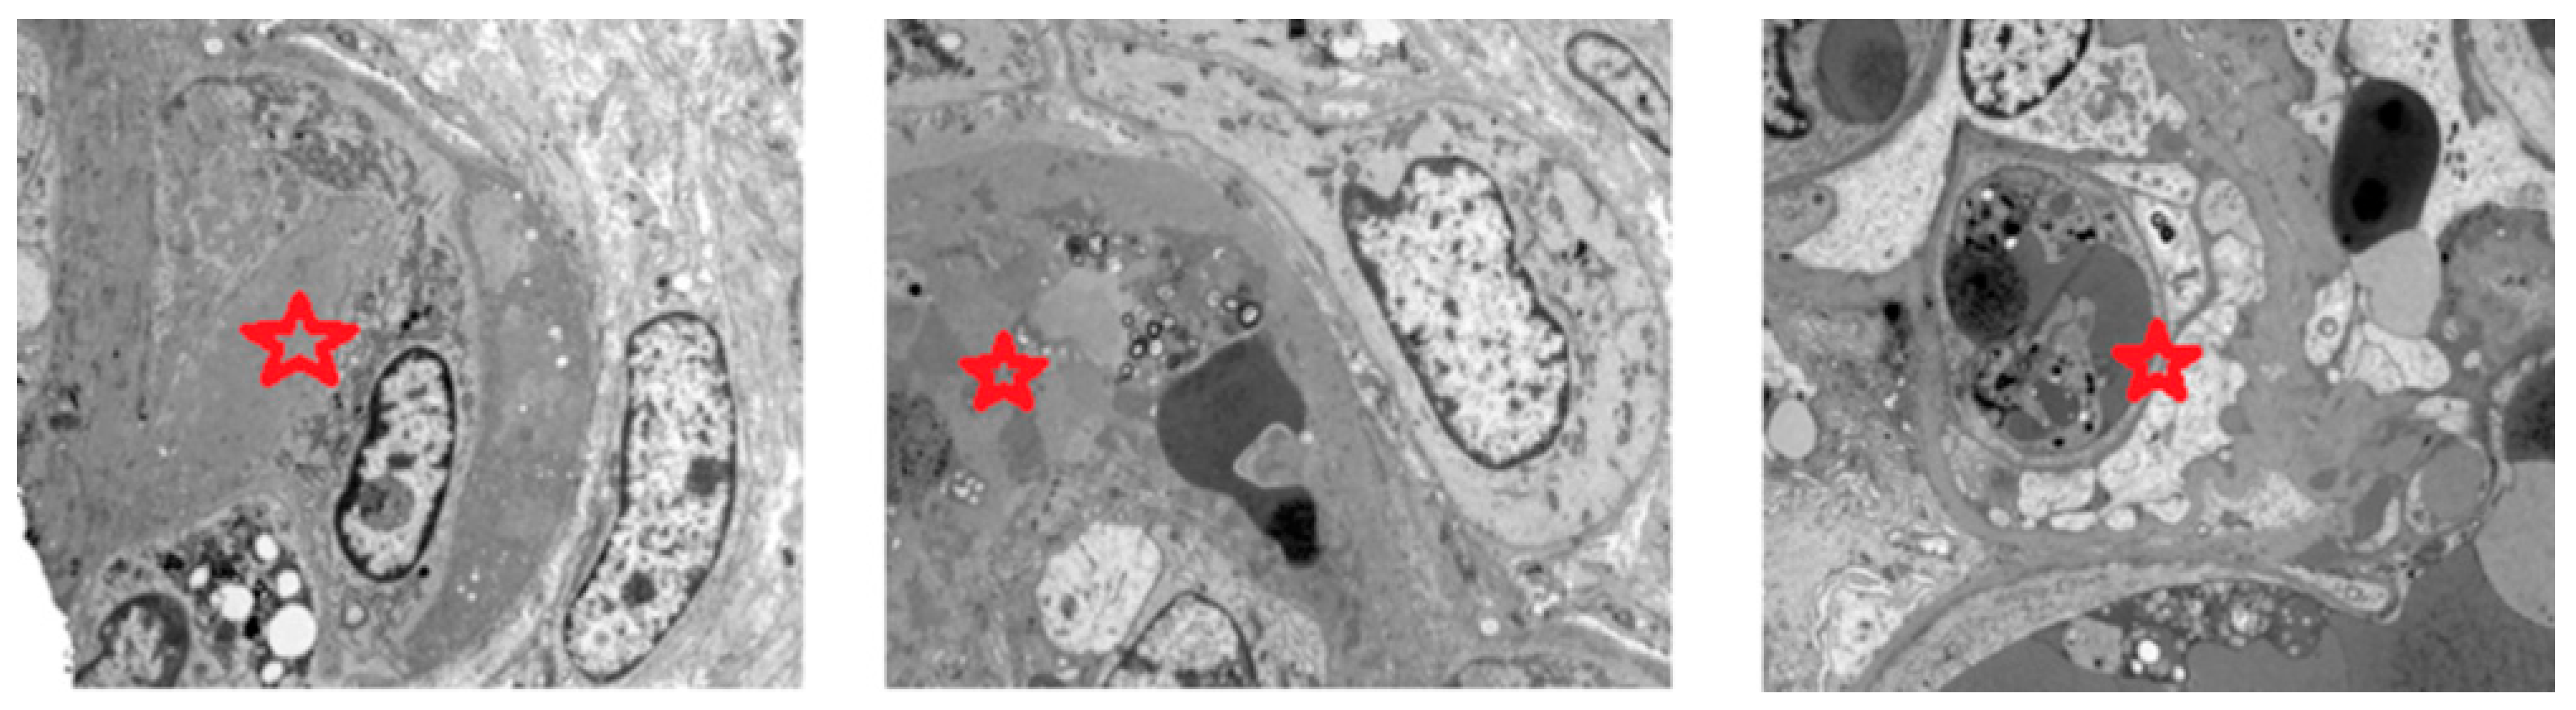

3.2. APS-Associated Nephropathy